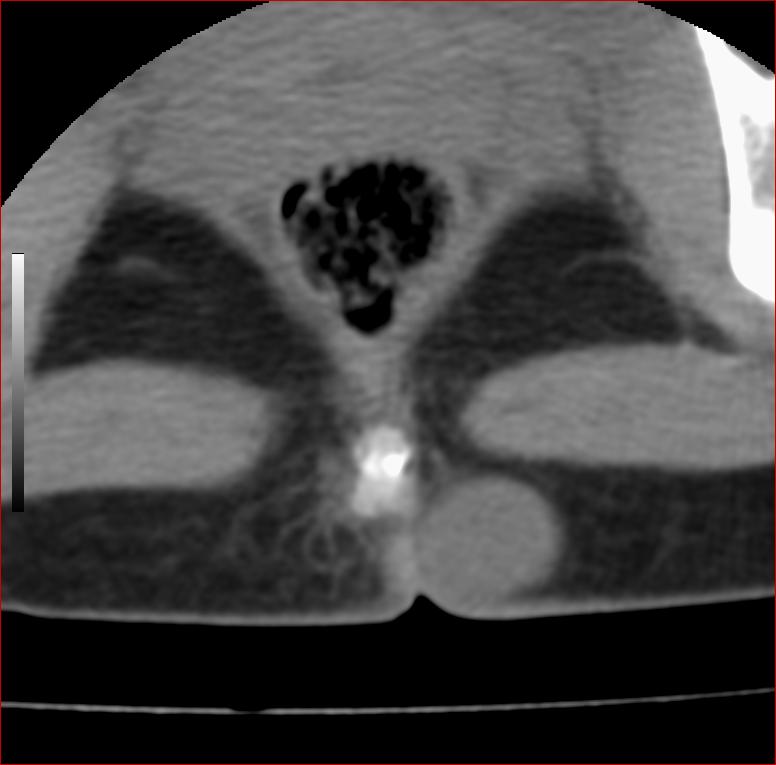

以下是引用13081830109在2007-5-16 18:51:00的发言:[br]良性病变[br]1.皮下皮脂腺囊肿[br]2.纤维瘤[br] 手术切掉就可以了

以下是引用zhangzhongshou在2007-5-16 18:21:00的发言:[br]皮下囊肿可能性大

以下是引用一个人在2007-5-16 20:35:00的发言:[br]1.皮下皮脂腺囊肿[br]2.纤维瘤[br]

以下是引用xulianj在2007-5-16 22:03:00的发言:[br]1皮下皮脂腺囊肿[br]2纤维瘤[br]3还需要除外发育畸形,如脊膜膨出。